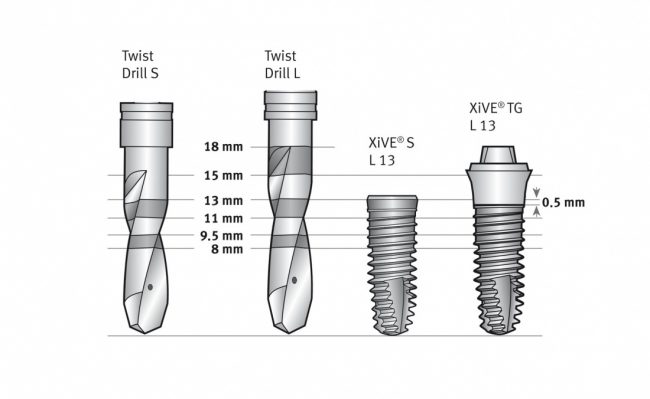

Другие компании-производители включают компоненты для протезирования (как минимум, для временного) в хирургический набор. Обычно это делают для систем, предназначенных для немедленной имплантации и т. н. «немедленной нагрузки». Такими являются, например, XiVE:

Отдельная тема — это тип фрез, используемых для подготовки лунки. Глобально, их можно разделить на два типа:

или XiVE:

2. Фрезы, калиброванные по глубине погружения. Например, Nobel Biocare:

или всё тот же XiVE, но под навигационные системы:

Казалось бы, со вторым типом фрез работать проще — не нужно париться с глубиной погружения и следить за отметками. Однако, при работе в тесных условиях, с ними могут возникнуть сложности — рабочая часть фрезы, конечно, откалибрована по длине, а вот хвостовик (та часть, которая вставляется в наконечник) у всех фрез одинаковый. И, возможно, потребуется специальный удлинитель для того, чтобы подготовить лунку под имплантат правильно: